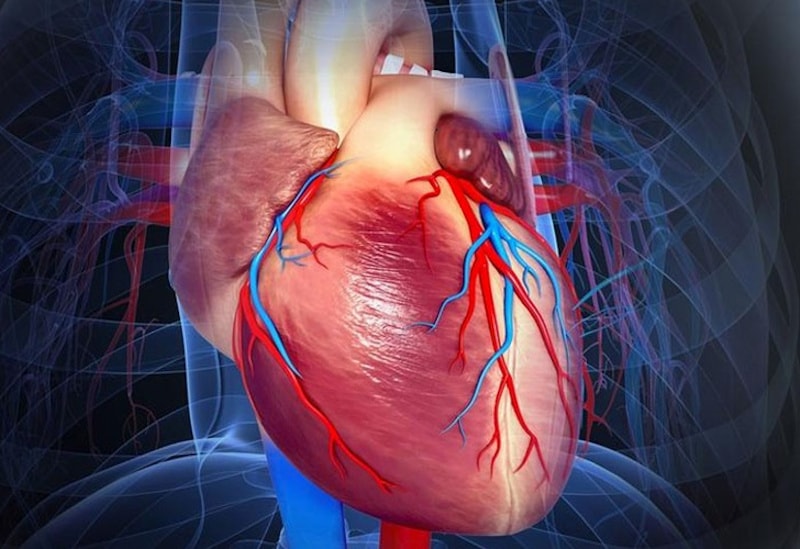

El corazón es un órgano muscular hueco compuesto por cuatro cavidades: dos aurículas en la parte superior y dos ventrículos en la parte inferior. El objetivo principal del corazón es bombear sangre a través del sistema circulatorio para suministrar oxígeno y nutrientes a los tejidos y eliminar los productos de desecho. El trabajo sistólico del corazón se refiere específicamente al trabajo realizado por los ventrículos durante su contracción, cuando expulsan la sangre hacia las arterias.

El trabajo mecánico realizado por el corazón se basa en el principio de la conservación de la energía. Durante la sístole ventricular, el músculo cardíaco se contrae y ejerce una fuerza sobre la sangre en los ventrículos, impulsándola hacia las arterias. A medida que la sangre es expulsada del corazón, se realiza trabajo mecánico contra la resistencia de las arterias y la presión arterial para vencer la resistencia vascular y mantener el flujo sanguíneo adecuado en todo el cuerpo.

Es importante destacar que el trabajo sistólico del corazón es un componente clave de la función cardíaca, ya que representa la capacidad del corazón para generar la fuerza necesaria para superar la resistencia vascular y mantener un flujo sanguíneo adecuado en todo el cuerpo. La cantidad de trabajo sistólico también puede variar en función de factores como la frecuencia cardíaca, la contractilidad del músculo cardíaco y la presión arterial, lo que refleja la adaptabilidad del corazón a las demandas cambiantes del organismo.

Concluyendo, el trabajo sistólico del corazón es la energía que el corazón utiliza para realizar trabajo mecánico durante la fase de contracción ventricular, bombeando sangre hacia las arterias para mantener la circulación sanguínea en el cuerpo. Este concepto es esencial para comprender la función cardíaca y la interacción entre el corazón y el sistema vascular.